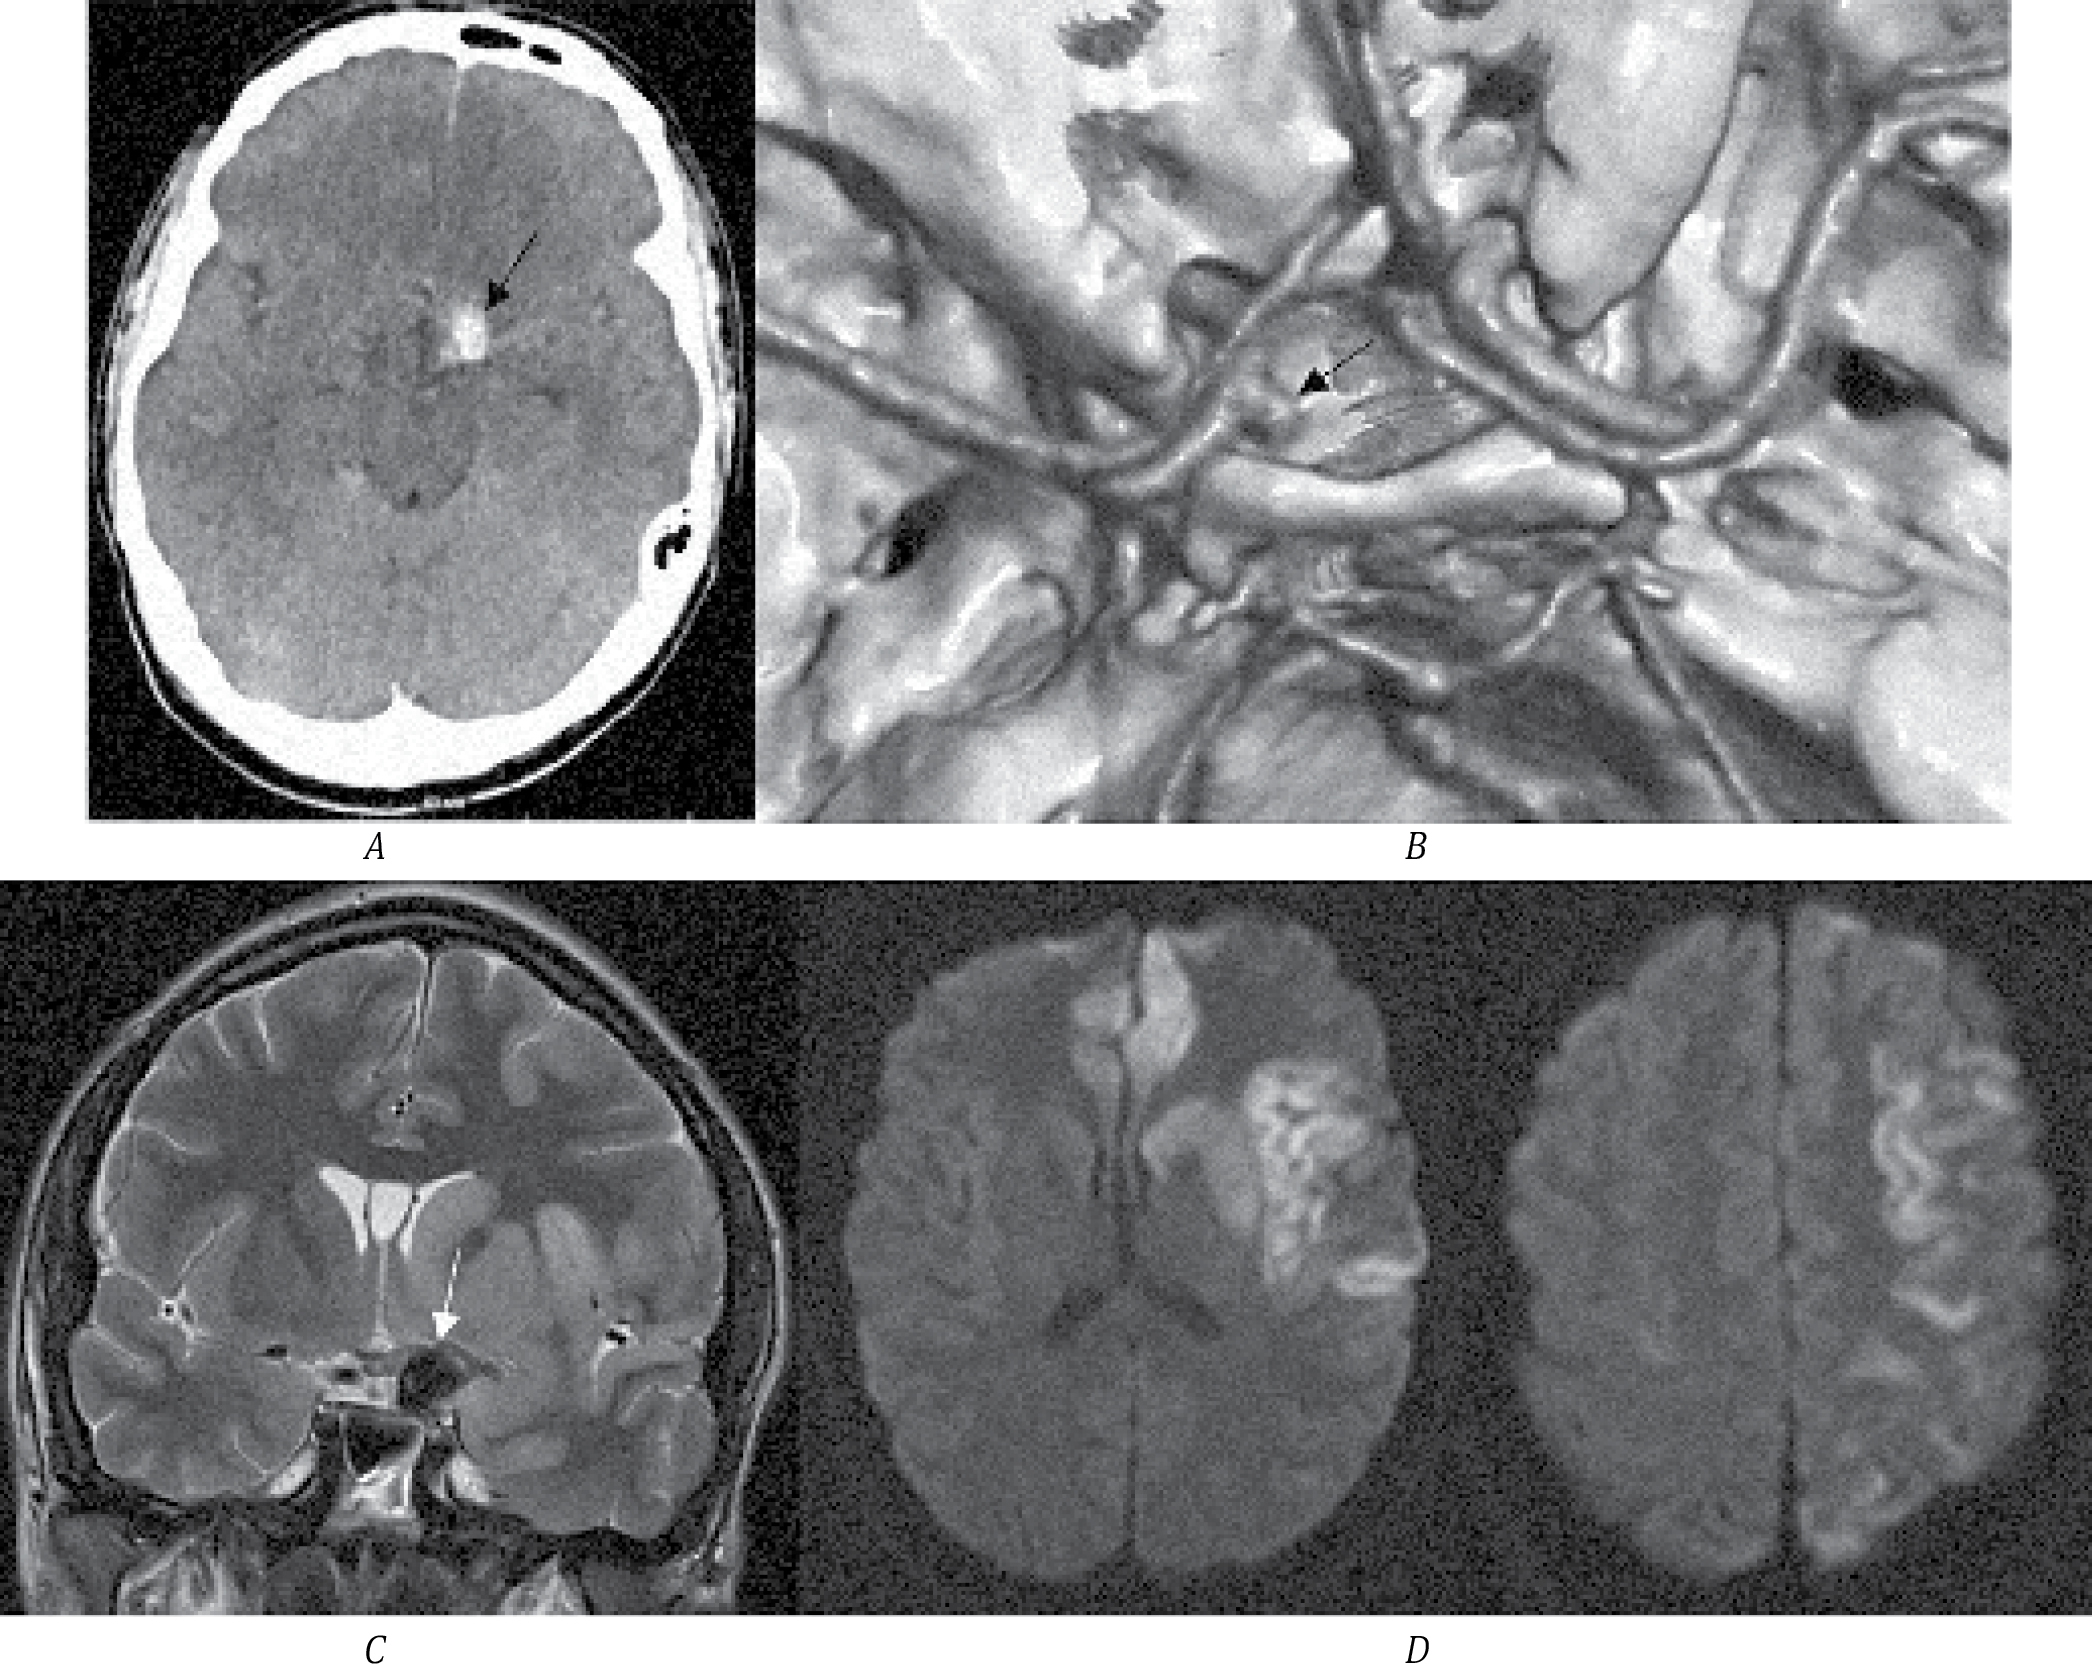

Пациентка И., 22 года, доставлена скорой помощью с жалобами на слабость и неловкость в правых конечностях. На момент осмотра — в ясном сознании, правосторонний гемипарез до 3,5 балла в руке, 4 баллов в ноге. По МСКТ определяется округлое образование гиперденсной плотности в проекции сильвиевой щели, подозрение на ТА. Обращает на себя внимание, что образование имеет разную плотность, в том числе участок высокой плотности, как возможный признак острого тромбоза (рис. 3, А). По МСКТ-ангиографии отсутствует кровоток в СМА слева, функционирующей части аневризмы не определяется. Учитывая лёгкий неврологический дефицит (5 баллов по NIHSS), острый тромбоз аневризмы СМА вместе с несущей артерией маловероятен. Пациентке выполнено МРТ головного мозга. Определяется большая ТА СМА, тромбоз СМА на всём протяжении. В области внутренней капсулы определяется участок ишемии, который соответствует развившемуся неврологическому дефициту у пациентки. На основании этого вероятно, что тромбоз аневризмы СМА вместе с артерией является хроническим, а в настоящее время клиническая картина вызвана развитием ишемии в подкорковых структурах, кровоснабжаемых лентикулостриарными артериями. Механизм развития ишемии в данном случае может быть связан как с эмболией тромбами, так и с увеличением размера аневризмы (наличие свежего тромба) и механическим перекрытием артерий.

Рис. 3. МСКТ головного мозга пациентки И.

А — стрелкой обозначена ТА; B — МСКТ-ангиография, белой стрелкой обозначено отсутствие кровотока в левой СМА; C — МРТ Т2-ВИ, стрелкой обозначена ТА СМА; D — МР-ангиография, отсутствие кровотока в СМА слева (указано стрелкой); E, F — МРТ Т2-ВИ и DWI, стрелкой обозначен очаг ишемии в области внутренней капсулы.

Других факторов риска инсульта у молодой пациентки не выявлено. Для определения тактики ведения выполнена церебральная ангиография и МСКТ-перфузия. По данным ангиографии у пациентки хорошо развит коллатеральный кровоток. По данным МСКТ-перфузии значимой разницы капиллярного кровотока в обоих полушариях нет. Принято решение о консервативном ведении пациентки с динамическим ангиографическим контролем. Осмотрена в динамике через 6 мес, повторных эпизодов ишемии у пациентки не было, функциональный статус оценён как 0 баллов по модифицированной шкале Рэнкина. На фоне приёма антиагрегантной терапии по МСКТ-ангиографии признаков реканализации аневризмы и средней мозговой артерии нет.